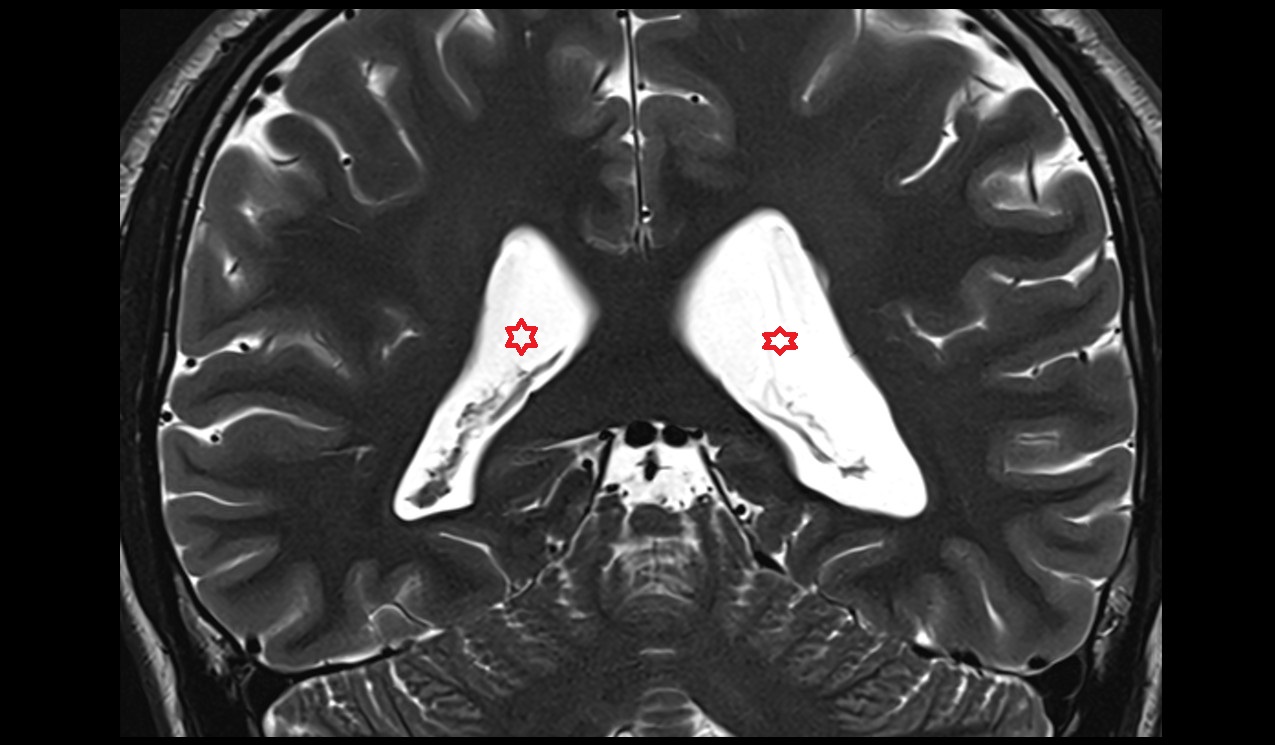

- Atrium of lateral ventricle

- Frontal horn of lateral ventricle

- Temporal horn of lateral ventricle